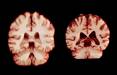

مغز زنان کُندتر پیر میشود، اما به نظر نمیرسد که این موضوع آنها را از ابتلا به نوع شایع زوال عقل محافظت کند. به گزارش ایسنا به نقل از نیچر، بر اساس یک مطالعه طولی که امروز در مجموعه مقالات آکادمی ملی علوم منتشر شد، در طول پیری، مردان در مقایسه با زنان، کاهش حجم بیشتری را...